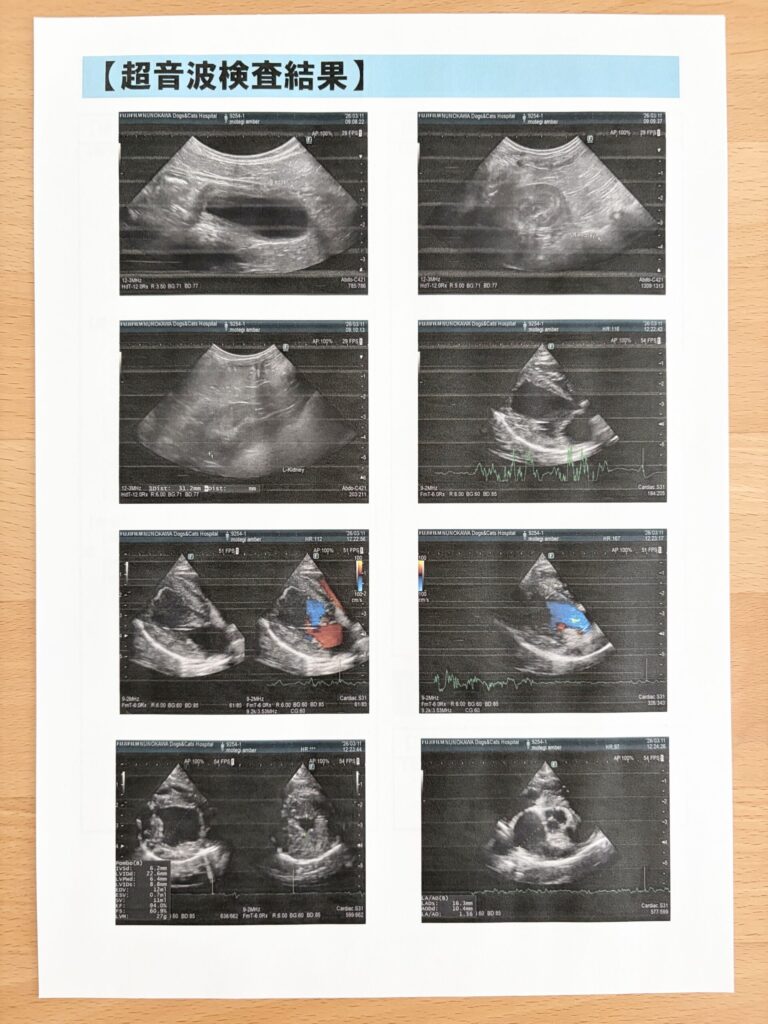

今年も“わんにゃんドッグ”を受けてきたよ、10歳になったこともあり基本コースと循環器(心臓、腎臓)も初検査

朝食を抜いて8:30に来院〜15:00にお迎え、ボク頑張ったぞ!!検査結果はこちら

いつもの皮膚、首腰以外は心臓僧帽弁に少〜し逆流がみられるけど今のところは問題なしでひと安心…